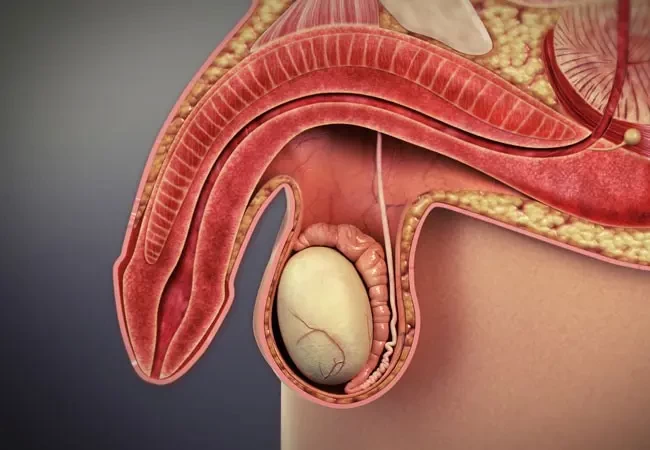

The three systems of an erection

For an erection to happen — and stay — three systems have to work together:

Blood flow in – arteries must open wide enough to flood the penis with blood.

Blood stay – tiny valves in the veins must lock shut, trapping the blood inside.

Signals from the brain – nerves must fire clearly, telling the body “now is the time.”

When these three align, you get a natural, reliable erection.

When even one fails… firmness collapses.

How they break down

Damaged blood vessels: age, stress, high cholesterol or diabetes narrow the arteries, starving the penis of blood.

Weak valves: veins can’t hold the pressure, so the blood escapes within minutes.

Silent nerves: after surgery, illness, or simply time, the nerves go numb, cutting off the vital signal from the brain.